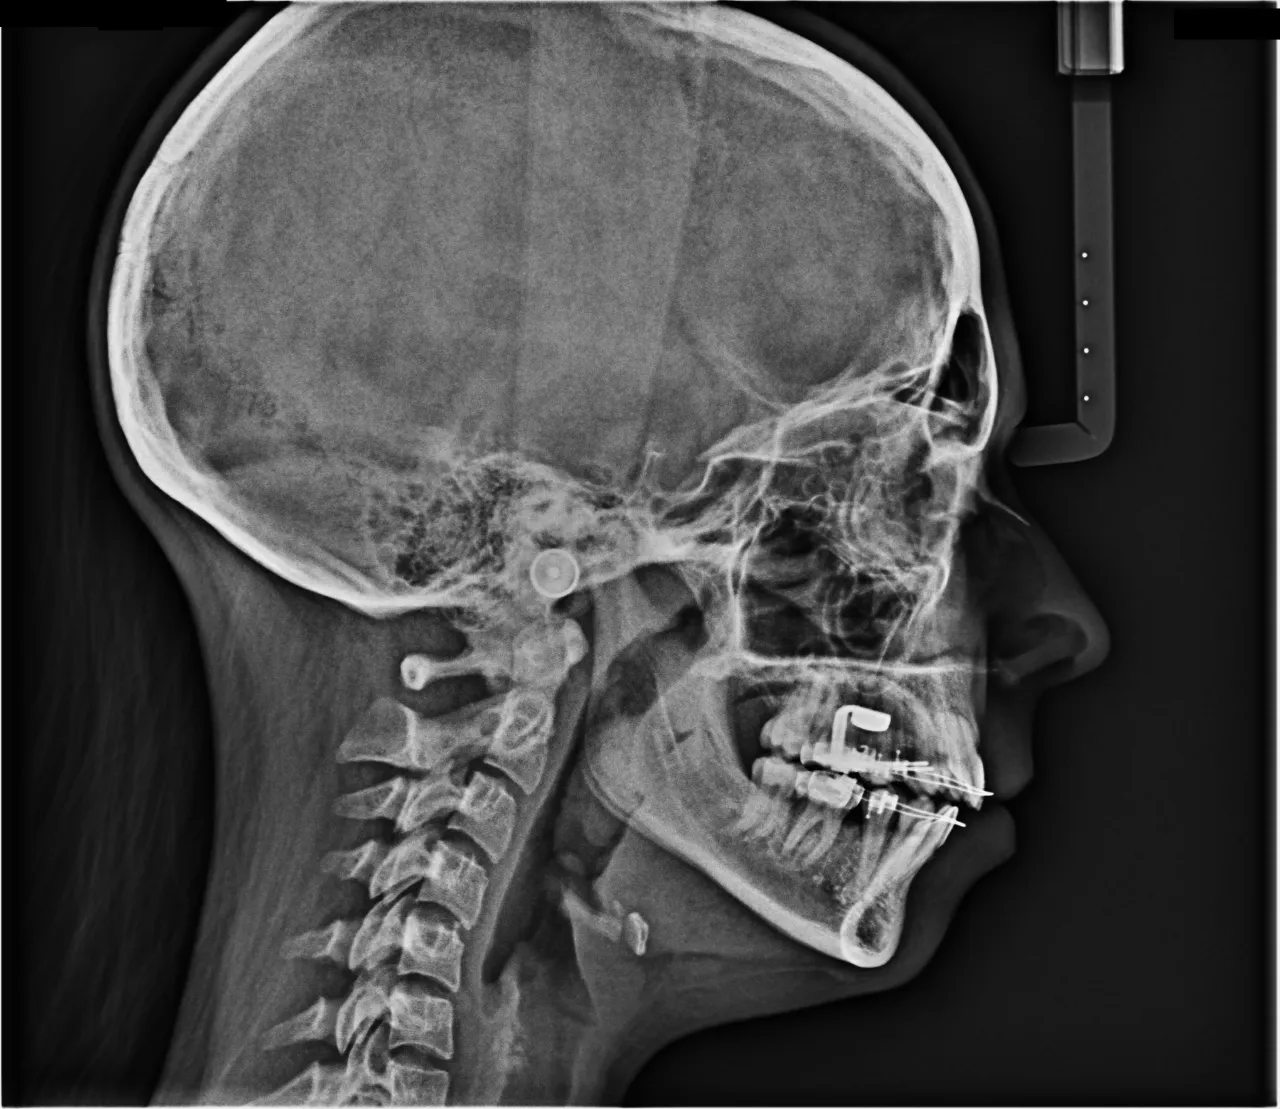

Diagnostyka obrazowa: Dlaczego zdjęcia RTG (pantomogram, cefalometria) są niezbędne?

Zdjęcia rentgenowskie to absolutna podstawa w diagnostyce ortodontycznej. Pantomogram (zdjęcie panoramiczne) pozwala mi ocenić stan wszystkich zębów, ich korzeni, zawiązków zębów stałych (u dzieci), a także kości szczęk i stawów skroniowo-żuchwowych. Zdjęcie cefalometryczne, czyli boczne zdjęcie czaszki, jest z kolei kluczowe do analizy proporcji twarzy, pozycji szczęk względem siebie i podstawy czaszki. Dzięki tym zdjęciom mogę precyzyjnie zaplanować kierunek przemieszczania zębów i przewidzieć, jak wpłynie to na rysy twarzy pacjenta. Bez nich leczenie byłoby jak nawigowanie bez mapy.Wyciski czy skan 3D? Jak powstaje cyfrowy model Twojego uśmiechu